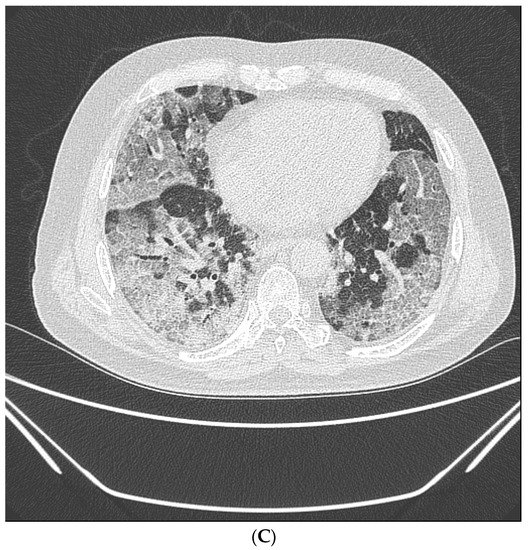

LDCT were obtained on symptomatic patients at high risk of screening with a 64-section scanner (Brilliance CT, Philips Healthcare) [16]. One radiologist (over 15 years of experience) and one pulmonology specialist (over 8 years of experience) retrospectively reviewed all LDCT images. Lobar distribution was assessed by observing the number of involved lobes, laterality, cephalocaudal distribution, and axial distribution [17]. In terms of pattern, ground glass opacity (GGO), consolidation, and crazy-paving pattern was assessed according to the definitions based on the Fleischner Society Nomenclature Committee recommendations [17,18]. (Figure 2A–C) Observation of the following characteristics was considered a typical finding for COVID-19; (1) peripheral, bilateral, GGO with or without consolidation or visible intralobular lines (“crazy-paving”), (2) Multifocal GGO of rounded morphology with or without consolidation or visible intralobular lines (“crazy-paving”), (3) Reverse halo sign or other findings of organizing pneumonia [18].

Figure 2.

Typical findings for COVID-19 on CT scans. (A) Ground-glass opacity shows as a modest increase in lung attenuation on lung window CT images, not obscuring the pulmonary vessels. (B) Consolidation appears as high-density patchy opacities that obscure the margins of vessels and airway walls, inside which air bronchogram (arrow) could be observed. (C) Crazy-paving pattern appears as thickened interlobular septa and intralobular lines superimposed on a background of ground-glass opacity.

3.4. Radiologic Findings on LDCT

The findings of LDCT in 355 symptomatic patients are summarized in Table 3. The κ values for inter- and intraobserver reliability ranged from 0.939 to 0.995, indicating excellent agreement (p < 0.001). Of the symptomatic patients, 25.9% (n = 92) had any type of pneumonia. Of these, 22 patients were diagnosed with COVID-19 using RT-PCR. Of patients diagnosed with pneumonia through LDCT, typical COVID-19 findings were found significantly in the positive RT-PCR group (p < 0.001). Furthermore, the density on LDCT was significantly different between the COVID-19 group confirmed by RT-PCR and the non-COVID-19 group (p < 0.001). The GGO pattern was found more frequently in the positive RT-PCR group (50.0%), whereas consolidation was found more frequently in the negative RT-PCR group (54.3%).